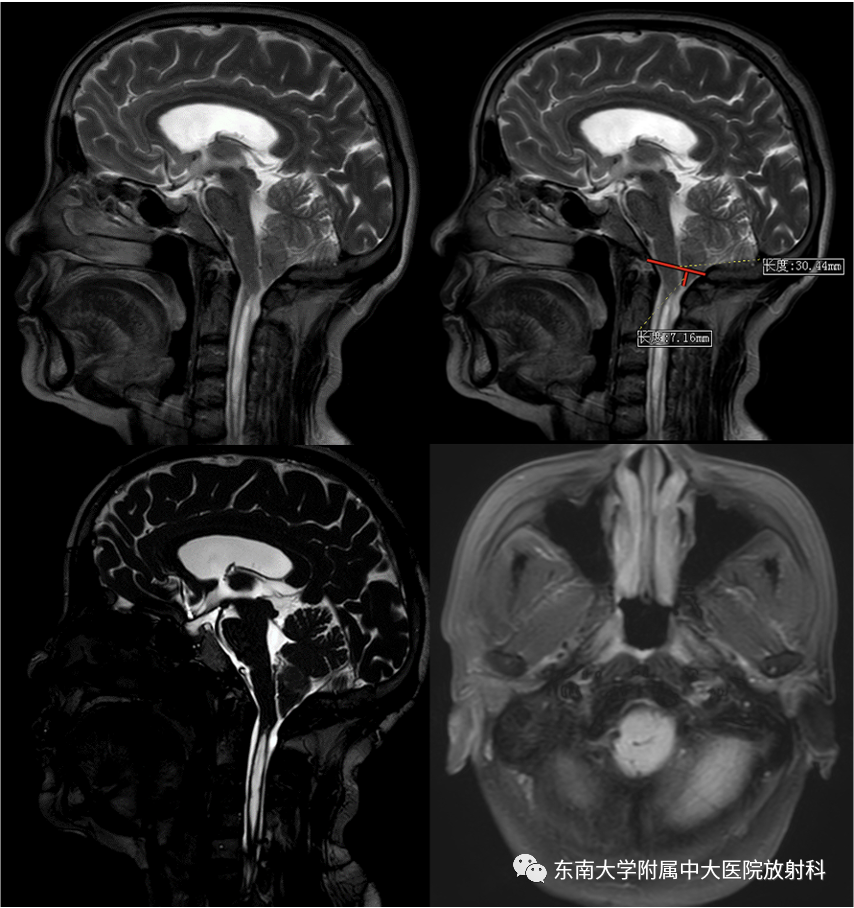

【PPT】小脑扁桃体下疝畸形

病史

女性,59岁

主诉:左侧肢体乏力、感觉减退20 余年

病史:患者20余年前无明显诱因下出现左侧肢体乏力,尚不影响体力活动,休息无明显缓解。左侧肢体感觉减退,表现为对疼痛不敏感,感觉不到热水的温度,左侧躯体皮肤出现烫伤而不自知。时有左下肢抽动样疼痛,数分钟后可缓解。有头痛,无头晕,无恶心呕吐,无黑蒙晕厥,无肩颈部疼痛,无明显肢体麻木,无饮水呛咳,无意识障碍,无大小便失禁。患者当时未予重视,未特殊治疗。现上述症状进行性加重,逐渐出现左上肢上抬受限